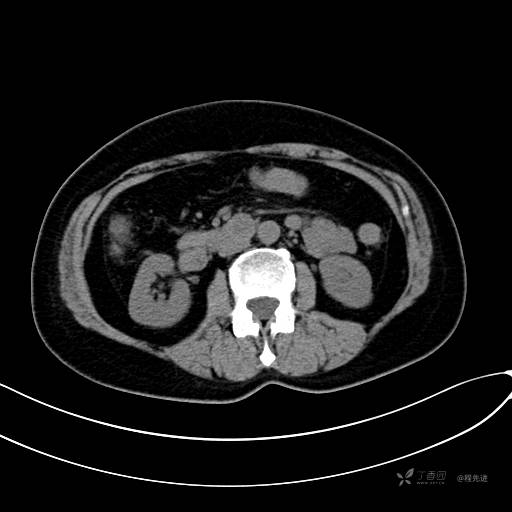

CT增强动脉期